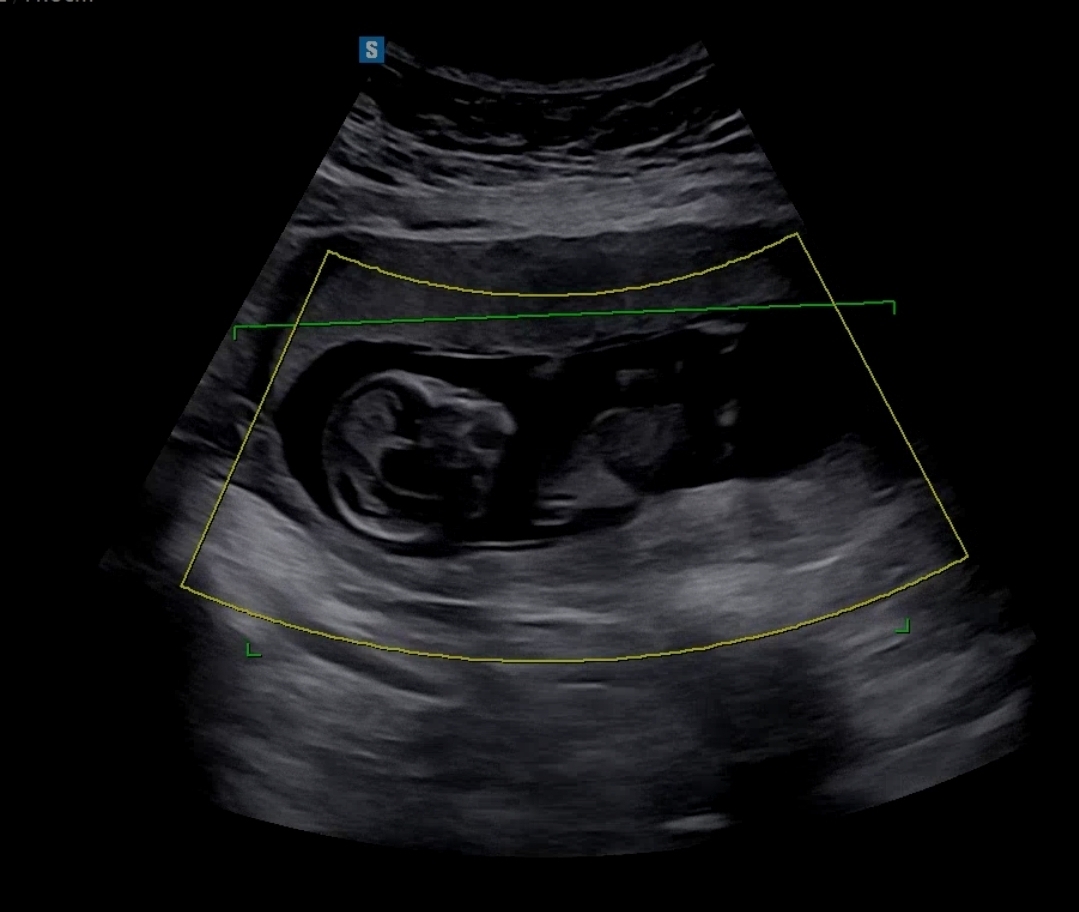

어제 찍은 초음파예요. 12주2일인데 각도법 부탁드려요😆